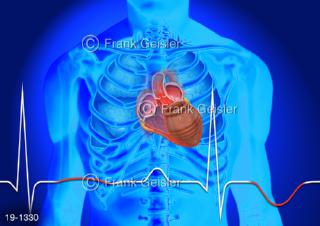

Bildergalerie Medical Art

Bilder zu Medical Art und Anatomie-Art, visuelle Darstellung medizinischer Inhalte künstlerisch umgesetzt, medizinisches Fachwissen als künstlerische Gestaltung für die Ausbildung, zur Patientenaufklärung und zur wissenschaftlichen Kommunikation, als künstlerische Dekoration in Gesundheitseinrichtungen und Arztpraxen